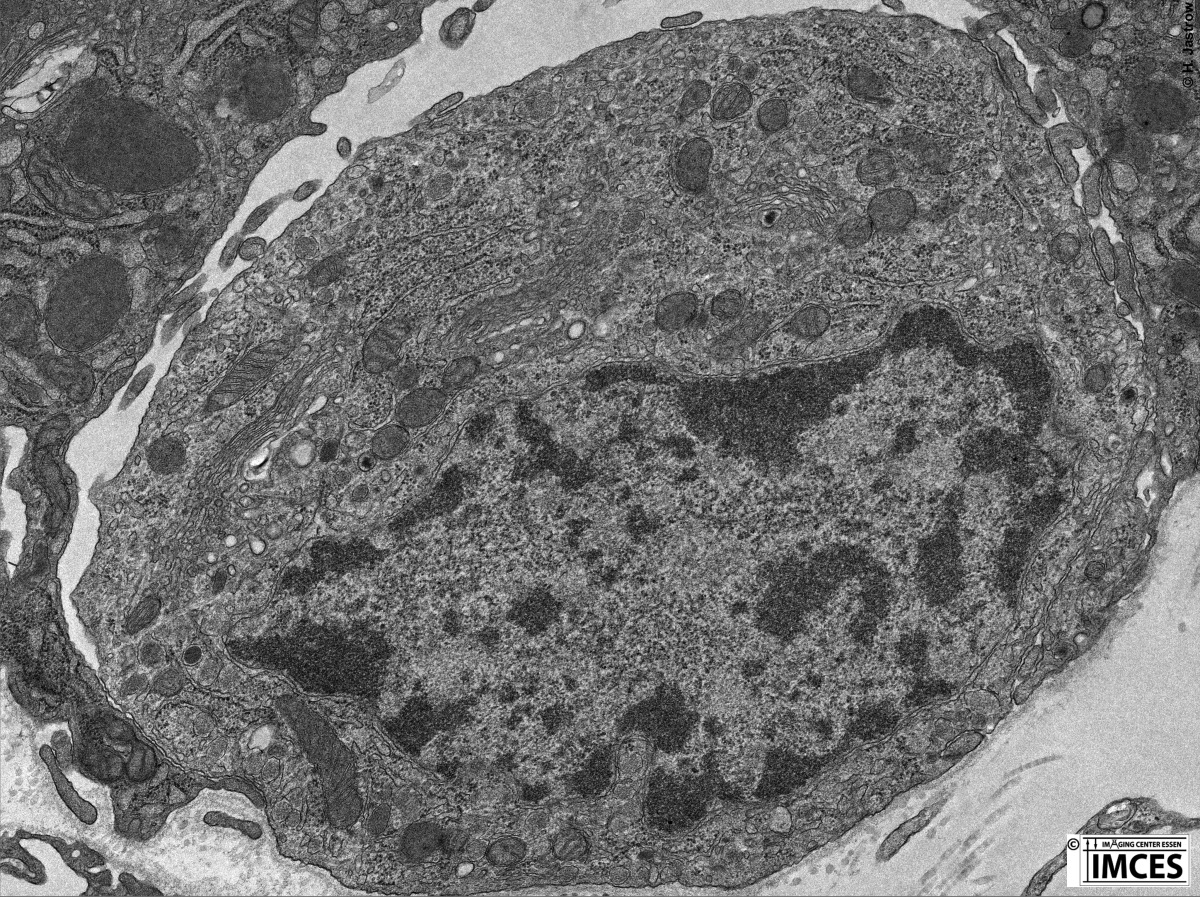

Transmissionselektronenmikroskopisches Demonstrationsbild (Aufnahme: H. Jastrow) JEOL 1400 Plus TEM

Dieses transmissionselektronenmikroskopische Bild zeigt eine Kalzitonin-bildende C-Zelle der Schilddrüse mit ihren Organellen.